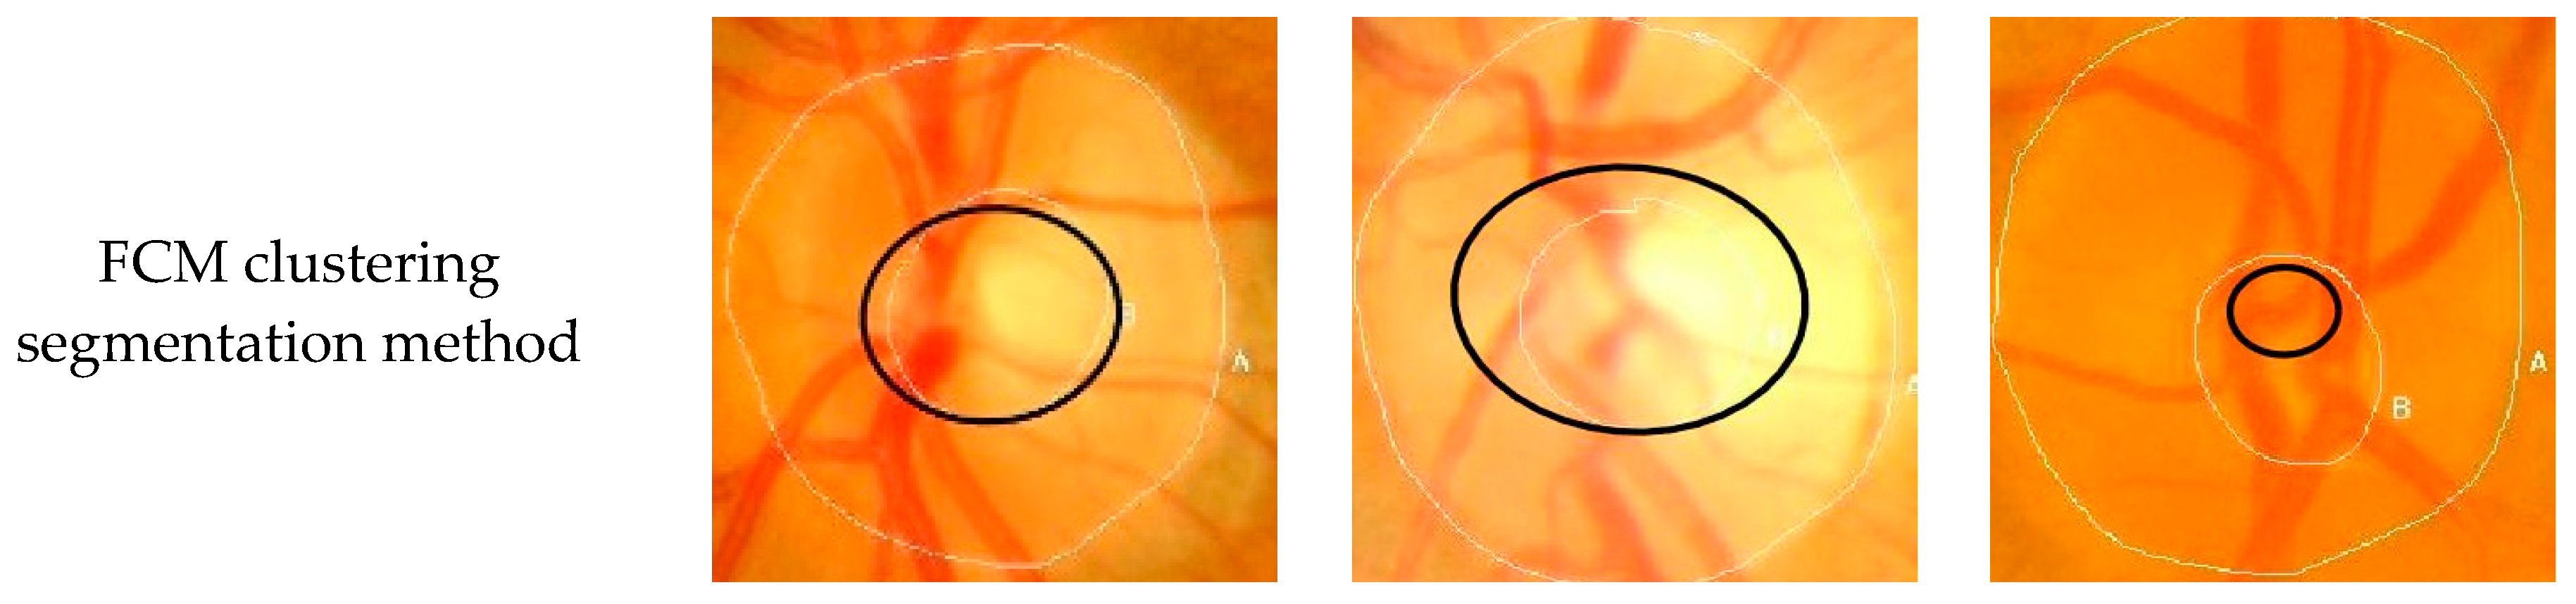

To verify the performance of the Seg-ResNet network-based optic cup segmentation method proposed in this paper, we compared our method to the FCM cluster segmentation method. The segmentation results are shown in Figure 9 and Figure 10.

• GlaucomaRepo database segmentation results.

• Drishti-GS database segmentation results.

The optic cup segmentation method, based on FCM clustering, fully considered the brightness information of the image and the characteristics of the blood vessel bending point falling on the edge of the optic cup. However, due to the complicated fundus image, the extraction of the optic cup needed to undergo a series of preprocessing steps, including disc segmentation, region of interest extraction, blood vessel extraction, blood vessel bending point detection, optic cup rough segmentation, and ellipse fitting. Each step was sequential, i.e., each operation was based on the previous operation. If the result of an operation was inaccurate, then it would have had a greater impact on the final result. The division of the optic cup by conventional methods would inevitably be compounded by each pre-processing operation. Figure 9 and Figure 10 show that the conventional method could not accurately divide the optic cup in cases of low cup plate contrast and severe vascular occlusion, while the segmentation effect on the Drishti-GS data set was poor. The results were likely affected by the fact that the GlaucomaRepo data set and the Drishti-GS data set were taken from different fundus cameras, thus the imaging quality varied greatly. The overall gray value of the Drishti-GS data set was low, the vascular occlusion was severe in most images, the method used for filling the neighborhood pixels was not obvious, the FCM optic cup clustering was affected by vascular interference, and the segmentation effect was below average. Traditional image processing techniques are difficult to change between these two data sets, so traditional image processing technology is less robust than the optic cup segmentation method. The depth-based learning method based on deep learning methods used a large number of data sets, where each image was taken from different cameras in different shooting environments. Thus, the feature extraction method had strong adaptability and also showed excellent segmentation effects in different test sets. Figure 9 and Figure 10 show optic cup segmentation using a depth-based learning method, which not only learned the brightness characteristics of the optic cup, but also learned the characteristics of blood vessel bending at the edge of the optic cup. This was seen in both the GlaucomaRepo data set and the Drishti-GS data set; this information could be used to accurately divide the optic cup. Table 3 and Table 4 compare the segmentation performance of the deep learning methods using two different traditional databases. Overall, optic cup segmentation based on depth-based learning methods had higher precision and robustness over the traditional image processing technology.

Figure 9. GlaucomaRepo database segmentation results comparison using the Seg-ResNet-based method and the FCM clustering optic cup segmentation method.

Symmetry 11 00933 g009aSymmetry 11 00933 g009b